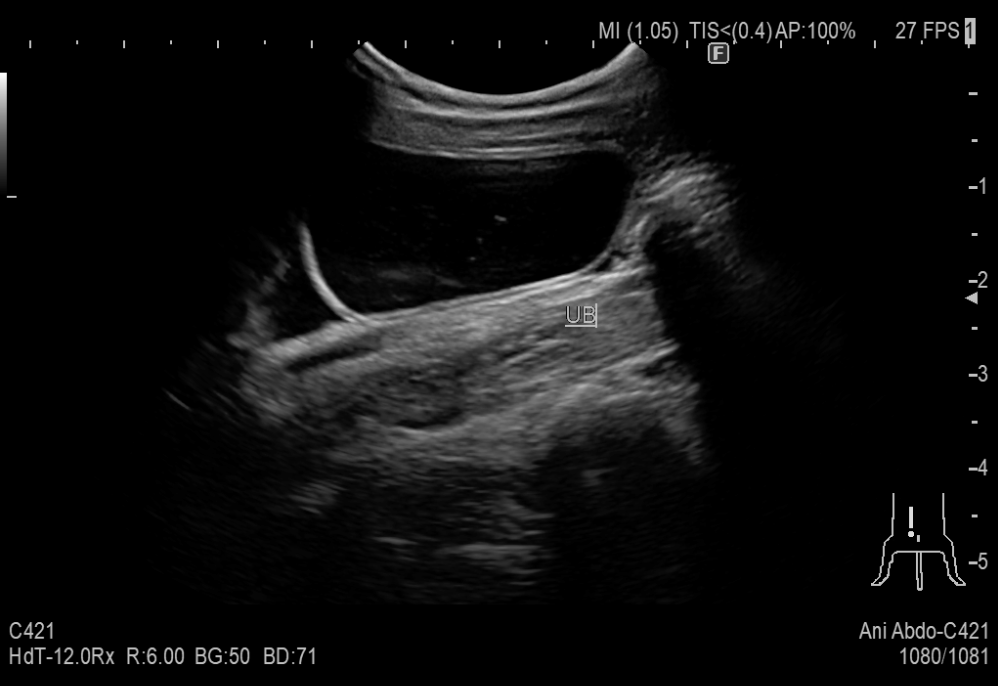

嘔吐を繰り返している8歳の猫が来院しました。

超音波検査にて消化管に腫瘍らしきできものが認められたため摘出を行いました。腹水が認められ、腹水の成分から腹腔内に炎症があることが分かりました。